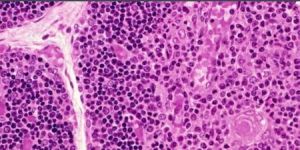

馬明海的心臟問題在於他的左右心房中間缺少間隔瓣,天生就合併成了一個,導致動脈血和靜脈血混在一起,讓他的皮膚看起來是紫色的,且血液粘稠容易缺氧。

由於心臟的原因,馬明海曾經突發腦梗塞,半個身子都幾乎癱瘓。在醫院治療期間,醫生從他的血管里抽血,抽得很吃力,抽了半天才抽出半針筒血,而且血是紫色的。別人的血像水一樣流暢,而馬明海的血卻像漿糊,粘稠得很。